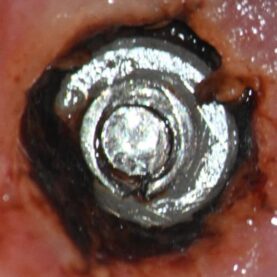

As the crown was still in place and noting from the intake form the abutment was from Atlantis, which like the OEM Ankylos abutments, has a free-floating laser assembled screw as the screw threads at M1.8 are larger than the through bore diameter of the abutment, 1.12mm. Therefore, the easiest way to access the implant top is to cut the head of the abutment screw off which releases the crown. The following preop. photo was taken at this point in the recovery. The photo on the right shows the edentulous space for a greater understanding of the thin fractured abutment cross section relative to the large mesial to distal space. This visually demonstrates the amount of mesial-distal space which translates into a huge amount of applied torsional loading onto the thin fractured cross section.

The abutment recovery was routine with reduction of the abutment screw down 3mm to expose the through bore. Next the through bore was tapped to M1.6mm, the distractor bolt was threaded into place and followed by placement of the distractor nut. The fractured conical portion of the abutment was then distracted and recovered. With microscope guidance, the remaining mobile abutment screw fragment was carefully rotated clear of the implant threads and recovered. The implant was cleaned, and the supplied healing abutment was placed finger tight. There was no visible implant damage when examined at 25x magnification. She was referred back to Dr. W. for treatment planning and future restoration.

At the patients request, post clinical appointment and prior to leaving, a detailed conversation was entertained as to why this abutment had failed in such a short time frame. The patient has not needed and therefore has had relatively little dental work to date, so the extraction of #30, implant placement and restoration with failure occurring so quickly, was troubling to her. As I evaluate all the implant abutment fractures in regard to duration in function, location of the fractured component, and the amount of fractured abutment material and type, this case was no exception. While it was no surprise to see another Ankylos abutment fracture on the schedule in a single tooth molar application, the very short time it took to fracture was interesting. The intake form listed this abutment as an Atlantis abutment, but it quickly was apparent this was not the case. The first clue was that tapping progressed rather quickly and while the threads were not deep, a slight eccentricity in the bore allowed for enough thread depth for successful distraction. Once the abutment fragment was recovered, the apical portion of the recovered abutment has a notched geometry as in the top of a castle. This can be appreciated in the above photo of the abutment fragment on the distractor. Ankylos and Atlantis abutments do not have this as the end of their abutments are not notched. This notching is due to a larger diameter through bore which invades the internal wall thickness in the indexing spline areas. While not Ankylos or Atlantis it is consistent for a non-OEM Glidewell abutment and possibly other non-OEM abutments as well. The following photo shows the recovered abutment fragment on the right and an intact Glidewell abutment on the left. Both are on a 1.78mm gage pin which goes completely through the Glidewell abutment and goes into the recovered abutment fragment until it hit a distorted area, secondary to the threading process. The stock Ankylos abutment has a through bore of 1.11mm vs. these at 1.78mm. So, you might say, so what? The problem is the Ankylos abutment has a maximum surface area of just 3.941 mm sq. and is ripe for fracture in this area. For comparison, a Dentsply Astra Tech EV 4.8mm implant and abutment has 9.96 sq.mm. With this Glidewell abutment, the area is reduced to 2.421sq. mm. I have never measured one this small previously. The smallest before this one was the Neodent CM interface, which is a copy of Ankylos for all practical purposes, and also has an enlarged through bore but at 1.51 mm sq. which nets out 3.118 sq.mm. These abutments also break at an accelerated rate. I believe the data is irrefutable. It might be argued this is the circuit breaker in the system to protect against implant fracture. Unfortunately, the analogy is like having a 40-amp circuit with a 5-amp circuit breaker. Almost any load will prematurely shut it down needlessly. She mentioned that a night guard was suggested. While this may help if she bruxes at night if she was able to engage posterior interferences and no anterior guidance, however, it will not protect her from loading secondary to mastication. I did not see an abundance of pathway wear to suggest a significant bruxing habit, nor did I see lateral excursive interferences. The only way I see to improve the stability of this implant / abutment connection is to use a solid abutment. This abutment will get the abutment cross section up to 4.91 mm sq. While this may work for a while, and clearly better than what was in previously, she has to understand two facts. One, I have recovered many fractured solid abutments as well, possibly 20 two-piece Ankylos abutments to one solid in approximately 220 fractured Ankylos abutment cases to date but recovering a solid is significantly more difficult to do without implant damage. Therefore, by restoring with a solid abutment it does not mean fracture is off the table. Unfortunately, I don’t have a better, simpler solution for this situation as the adjacent teeth are in good shape. I have been involved with three similar cases where the patient fractured a solid abutment rather quickly and the only real solution was to replace the implant with one that has a more overall robust mechanical connection such as a 4.8 EV.